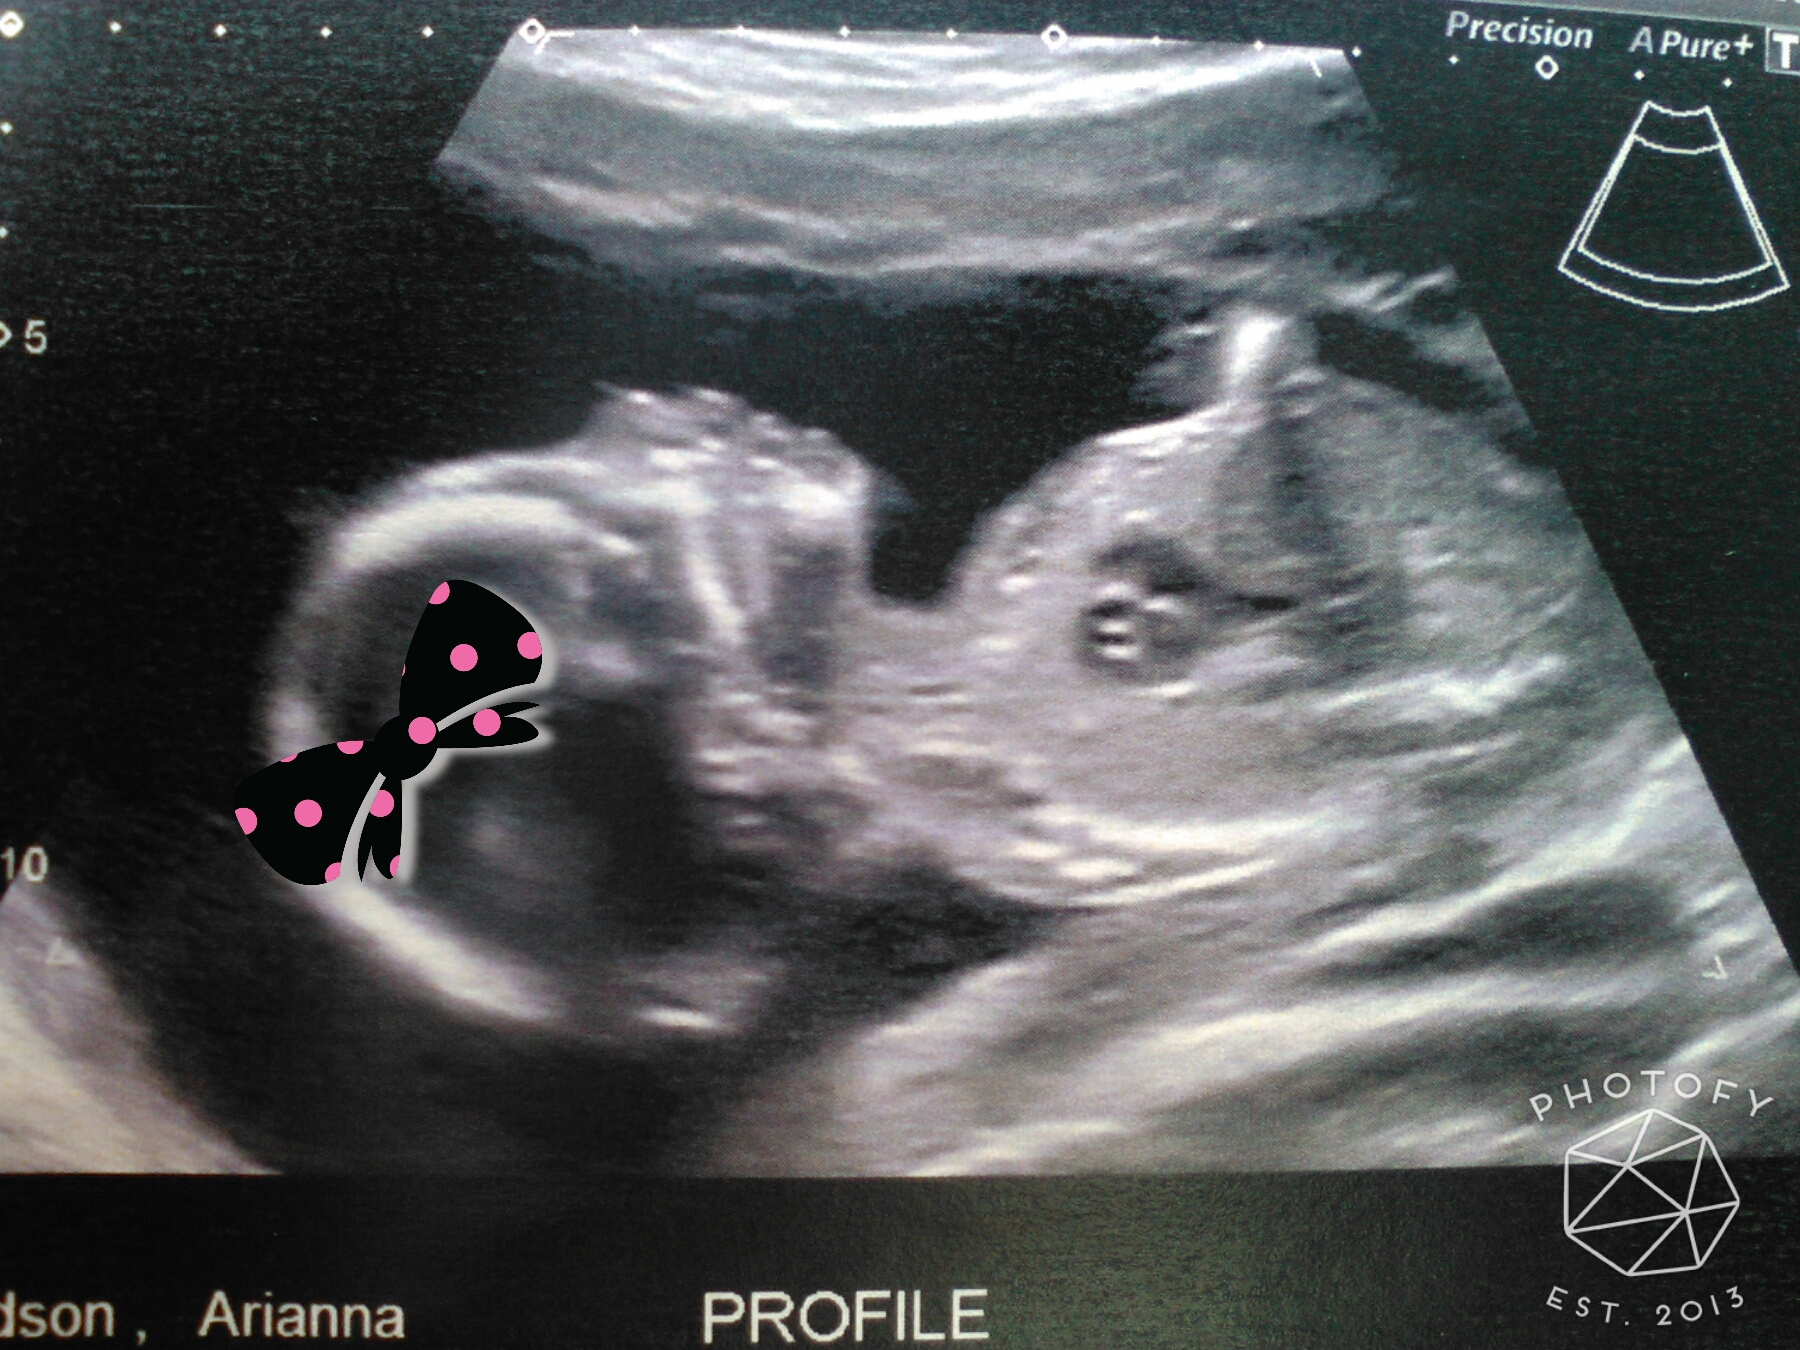

• We had our scan about a week ago, but I just realized this thread was here lol. Baby is on perfect health and we found out we're having a girl! She was kicking up a storm and we got to see her smile and wave at us. It was truly an amazing experience :\">

• I had my scan yesterday and we confirmed that she's definitely a girl, and she's definitely healthy! In fact, the doctor called her a "textbook perfect baby." Not sure how she'll ever live up to that label!

• This morning I confirmed my feeling that I'm having a girl!! :\">